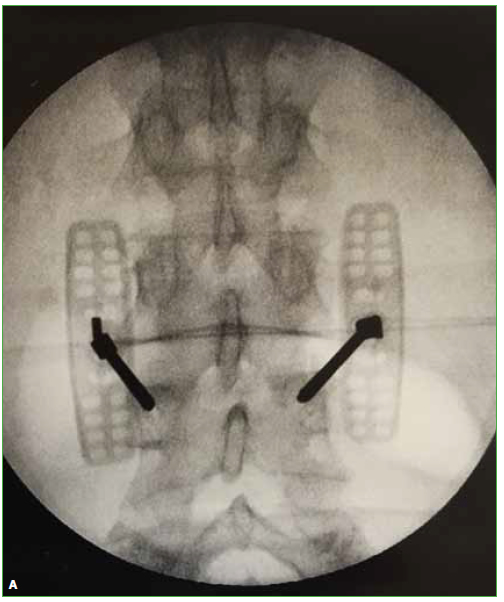

Hernia intraesponjosa de Schmörl sintomática. [Symptomatic intraosseous Schmörl herniation]